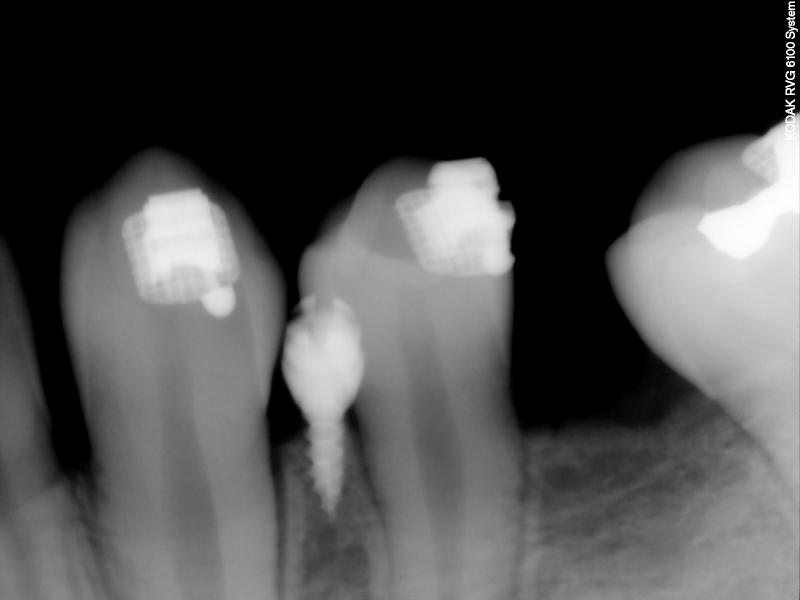

Fig. 2. The LLE is ankylosed.

© Copyright 2007-2014, Vu Orthodontics. All rights reserved.

Fig. 3. PA taken for TAD location (after LLE extracted)